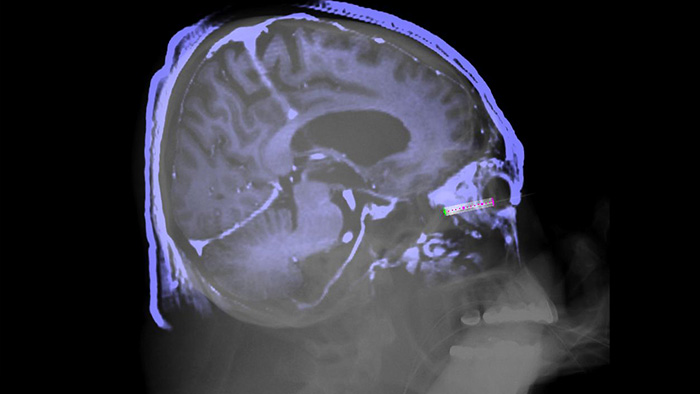

The SmartCT solution enriches our outstanding 3D interventional tools with clear guidance, designed to remove barriers to acquiring 3D images in the interventional lab. It simplifies 3D acquisition to empower all clinical users to easily perform 3D imaging, regardless of their experience1. Once acquired, 3D images are automatically displayed within seconds2 on the touch screen module in the corresponding rendering mode. On the same touch screen, the user can easily control and interact with advanced 3D visualization and measurement tools.

This X-ray acquisition technique generates a complete high-resolution 3D visualization of cerebral, cardiac, abdominal or peripheral vasculature from a single rotational angiography run – all controlled via the touch screen at the table. This can improve visibility of tortuous or complex anatomy.